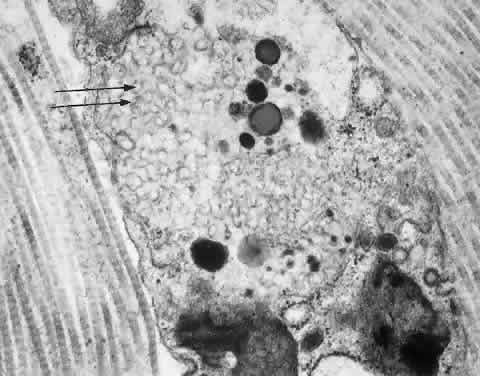

M (ed): Genetic and Metabolic Eye Disease, p 139. Boston: Little

syndrome) in human bone marrow. Proc Natl Acad Sci USA 93:2025, 1996 24. Scheie H, Hambrick GJ, Braner L: A newly recognized forme fruste of Hurler's disease (gargoylism): The

microscopic study. Invest Ophthalmol 12:366, 1973 137. Walton D, Robb R, Crocker A: Ocular manifestations of group A Niemann-Pick